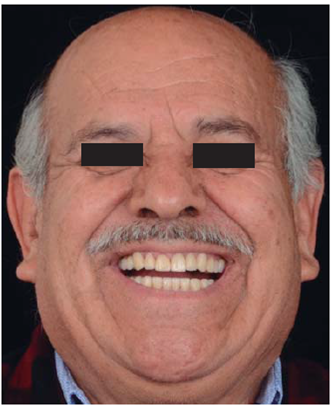

Este reporte documenta el tratamiento de un paciente masculino de 68 años de edad. Comenta tener dificultades masticatorias y digestivas debido a importante desgaste dental, se dice incómodo al sonreír; no refirió padecimientos sistémicos, fumó durante ocho años, diagnosticado con hipertensión arterial controlada. Se observa atrición generalizada, ausencia de dientes 14, 15, 16, 46 y periodonto sano (Figuras 1a4). Los dientes 13 y 37 presentaban tratamiento de conductos y periápice sano, sin restauración (Figura 5).

Para cuantificar la reducción de DVO, se examinó el perfil facial y la estética mediante análisis fotográfico y vídeo (Figuras 6y7). Además de realizar un cuidadoso análisis del montaje de los modelos diagnósticos en articulador semiajustable (Figura 8). También se examinó el esquema oclusal (presentaba relación borde a borde) y la estructura dental con la que se contaba (Figura 3). La revisión dinámica fue clave para determinar que el paciente exhibe una línea de sonrisa alta (Figura 9).

Se controló al paciente por espacio de un mes y medio para verificar su fase de adaptabilidad al tratamiento y su condición fue satisfactoriamente estable, cómoda y sobre todo funcional (Figuras 42a45).